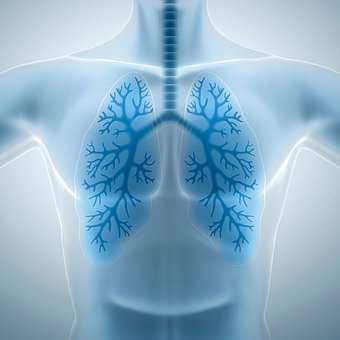

코나 입을 통해 들어온 공기는

인두와 후두를 거쳐 기관을 통하게 되는데.

기관은 좌우 기관지로 나뉘고

기관지는 다시 세 기관지들로 갈라져 폐와 연결된다.

림프절은 기관지를 따라 분포하며

원형 또는 완두콩 모양으로

세포 사이사이에 있는 물과

림프에 있는 미생물을 걸러내는 역할을 한다.